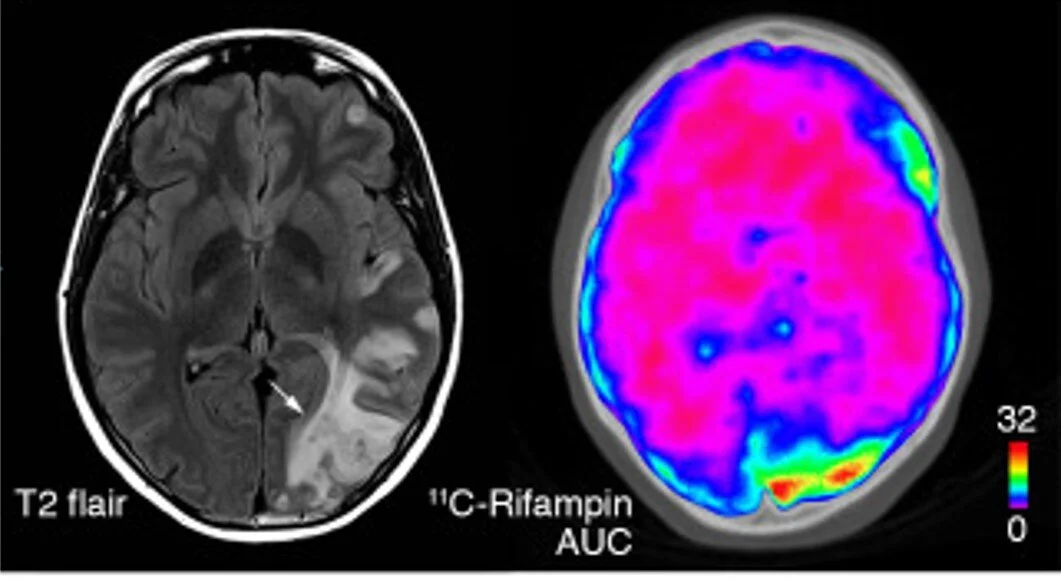

26.  DeMarco VP, Ordonez AA, Klunk M, Prideaux B, Wang H, Zhuo Z, Tonge PJ, Dannals RF, Holt DP, Lee CK, Weinstein EA, Dartois V, Dooley KE, Jain SK. Determination of 11C-Rifampin Pharmacokinetics within Mycobacterium tuberculosis-Infected Mice Using Dynamic Positron Emission Tomography Bioimaging. Antimicrob Agents Chemother. 2015 Sep;59(9):5768-74.

35.  Shaikh N, Gupte A, Dharmshale S, Pokkali S, Thakar M, Upadhye VJ, Ordonez AA, Kinikar A, Gupte N, Mave V, Kagal A, Gupta A, Lalvani A, Paranjpe R, Bharadwaj R, Jain SK. Novel interferon γ assays for diagnosing tuberculosis in young children in India. Int J Tuberc Lung Dis. 2017 Apr 1;21(4):412-419.

47.  Tucker EW, Guglieri-Lopez B, Ordonez AA, Ritchie B, Klunk MH, Sharma R, Chang YS, Sanchez-Bautista J, Frey S, Lodge MA, Rowe SP, Holt DP, Gobburu J, Peloquin CA, Mathews WB, Dannals RF, Pardo CA, Kannan S, Ivaturi V, Jain SK. Noninvasive 11C-Rifampin Positron Emission Tomography Reveals Drug Biodistribution in Tuberculous Meningitis. Sci Transl Med. 2018 Dec 5; 10(470): eaau0965. DOI: 10.1126/scitranslmed.aau0965

56.  Ordonez AA, Wang H, Magombedze G, Ruiz-Bedoya C, Srivastava S, Chen A, Tucker EW, Urbanowski ME, Pieterse L, Cardozo-Ojeda E, Lodge MA, Shah MR, Holt DP, Mathews WB, Dannals RF, Gobburu J, Peloquin CA, Rowe SP, Gumbo T, Ivaturi V, Jain SK. Dynamic Imaging in Tuberculosis Patients Reveals Heterogeneous Drug Exposures in Pulmonary Lesions. Nat Med. 2020 (in press).